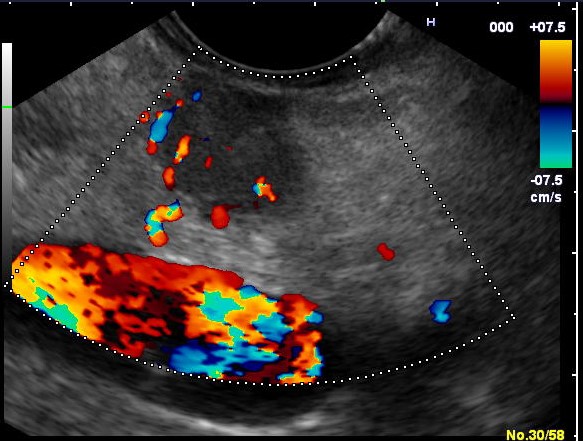

Ультразвуковое исследование при подозрении на гастриному проводится трансабдоминально в режиме серошкального сканирования с цветным и энергетическим допплеровским картированием, а также при необходимости дополняется эластографией и контрастным усилением. Обследование направлено на выявление гиперваскулярных очагов в поджелудочной железе и двенадцатиперстной кишке, характерных для гастрины-продуцирующих нейроэндокринных опухолей, вызывающих синдром Золлингера—Эллисона.

Ультразвуковое исследование выявляет следующие анатомические признаки гастриномы:

Очаговое гипоэхогенное или изоэхогенное образование овальной или округлой формы в проекции головки или тела поджелудочной железы, с чётким контуром и размерами от 5 мм.

Выраженный внутриили перифокальный сосудистый рисунок при цветном допплеровском картировании, соответствующий гиперваскулярной природе образования.

Увеличение поджелудочной железы без очагов при диффузном варианте гастриномы, с неоднородной эхоструктурой и усилением сосудистого рисунка.

Уплотнение и утолщение стенки желудка и двенадцатиперстной кишки за счёт гиперплазии слизистой, визуализируемое как многослойная гипоэхогенная структура.

Регионарная лимфаденопатия: гипоэхогенные лимфоузлы овальной формы с усиленным кровотоком, диаметром более 10 мм.